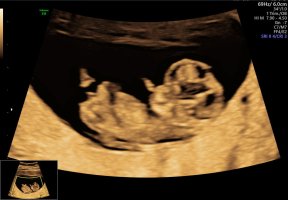

Alt såg bra ut på OTUL 12+3

Vis vedlegget 456172

100% gutt12+2 i dag. Hvilket kjønn tror dere?

Vis vedlegget 456403

Det så veldig ut som en gutt![]()